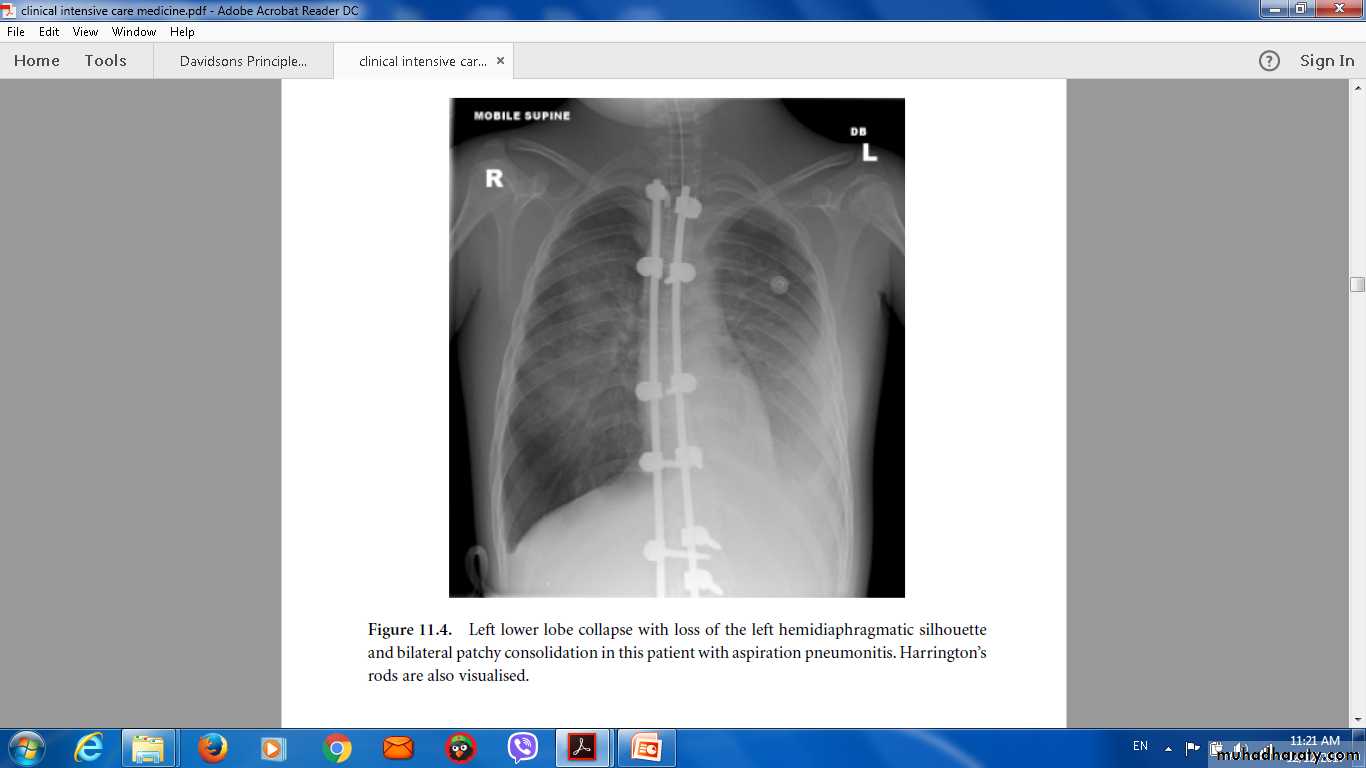

New radiological infiltrates.

These conditions are considered together, as their aetiology and clinical features overlapSuppurative pneumonia is characterised by destruction of the lung parenchyma by the inflammatory process .

vomitus during anaesthesia coma, particularly if oral hygiene is poor.

oesophageal reflux,

alcoholism.